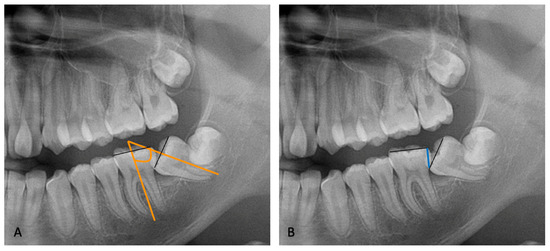

In the subjects treated with skeletal anchorage (Group B), after the germectomy of the third molar, a self-drilling miniscrew (BENEfit, psm, Tuttlingen, Germany) was inserted in the retromolar area just distal to the post-extraction socket of the third molar using a surgical contra-angle (iSD900; NSK, Tochigi, Japan) with torque control (maximum torque set at 40 N/cm). The insertion site and angle, as well as the length and diameter of the miniscrew, were planned before the procedure through measurements from orthopantomography. After the miniscrew insertion, two orthodontic brackets were applied to the molar crown, one on the vestibular surface and one on the lingual surface. Finally, an elastic chain was attached to the miniscrew head and the orthodontic brackets to create an elastic sling. Once the primary miniscrew stability and the effectiveness of the elastic sling traction (the elastic chain was elongated to about twice its original length) were both verified, the surgical site was completely sealed with submerged traction using sutures (Figure 3).

For the subjects treated with the traditional brass wire technique (Group A), follow-up visits were scheduled every 20 days, during which wire activations were performed until the uprighting of the MM2 was complete. In contrast, the Group B subjects had monthly follow-up visits until the complete uprighting of the MM2. The difference in the follow-up between the two groups is due to the need to periodically activate the brass wire to ensure the continuous movement of the MM2. In Group B, a longer follow-up was implemented because it was not necessary to reactivate the elastic chain. However, it remained important to monitor the patient for any potential complications, such as mini-implant failure or the detachment of the orthodontic button. In all cases treated with skeletal anchorage, there was no need to replace or reactivate the elastic chain, significantly reducing discomfort for the subjects. No miniscrew stability issues were observed in the Group B participants. The treatment was considered completed when the mesial marginal ridge of MM2 had passed the point of contact with the distal marginal ridge of MM1. The treatment time was recorded. A radiographic control was made before removing the orthodontic appliance in both groups (Figure 4). The advantages and disadvantages of the two techniques are shown in Table 1.

Figure 3. Surgical procedure using skeletal anchorage in Group B subjects. (A): mucoperiosteal flap and the exposure of the impacted second molar; (B): the exposure of the third molar; (C): the germectomy of the third molar; (D): miniscrew insertion; (E): the application of orthodontic brackets on the buccal and lingual surface of the mandibular second molar; (F): the application of the elastic chain.